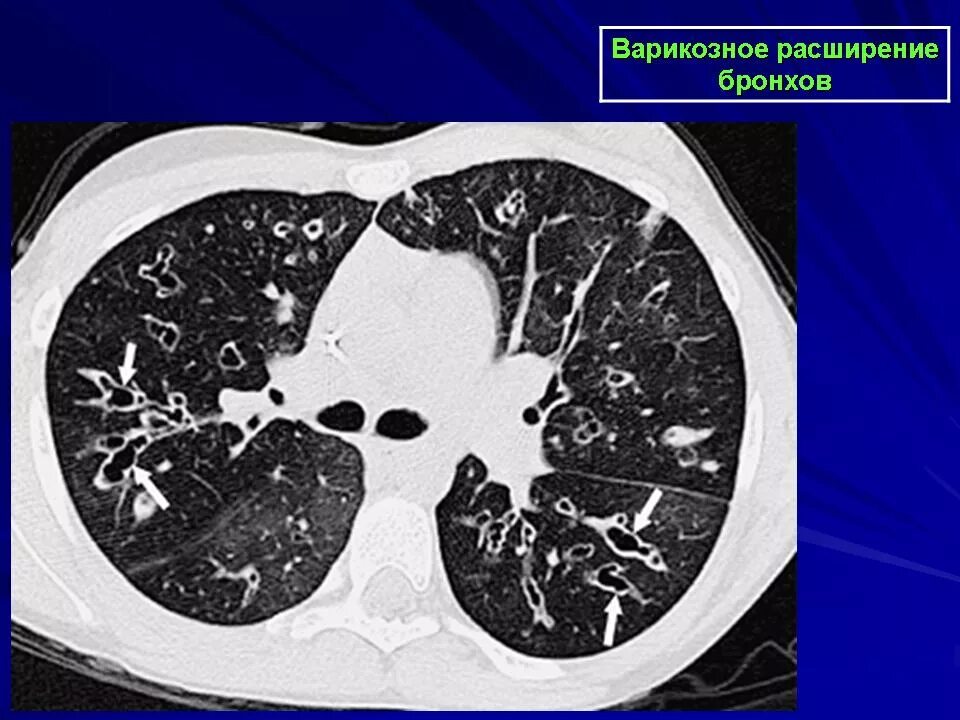

Утолщение бронха